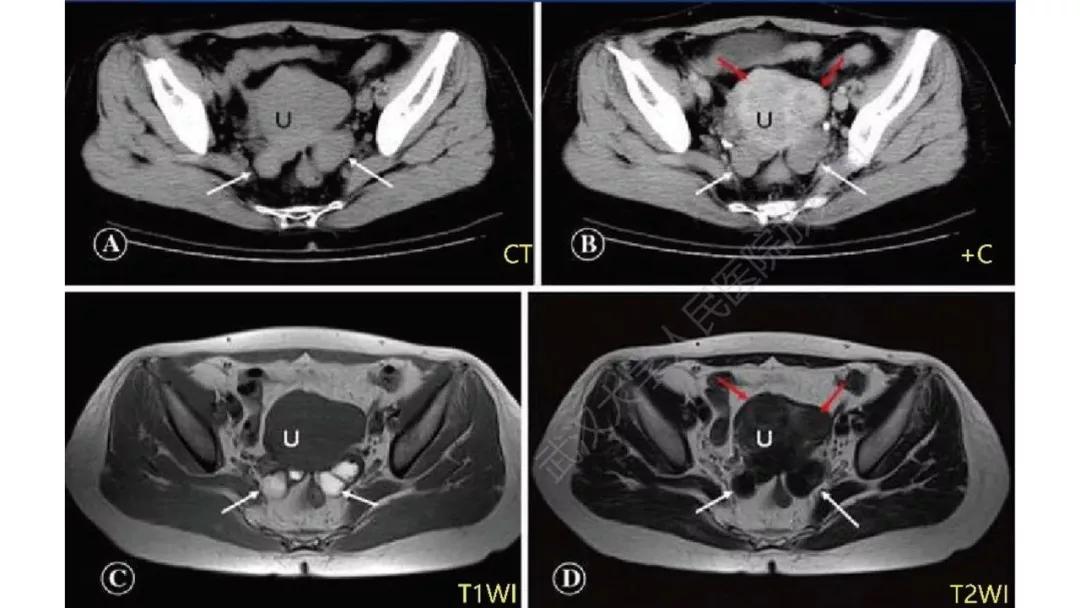

性索间质性肿瘤:较少见,良性多,多数肿瘤具有内分泌功能,可伴有内分泌症状及子宫内膜增生,内膜癌,乳腺疾病。多呈囊实性及实性肿块,界清,形态规则或欠规则,少有壁结节,多数呈实性伴有大片变性低密度改变,轻中度强化。

病理:颗粒细胞瘤

病理:左侧卵巢卵泡膜-纤维瘤